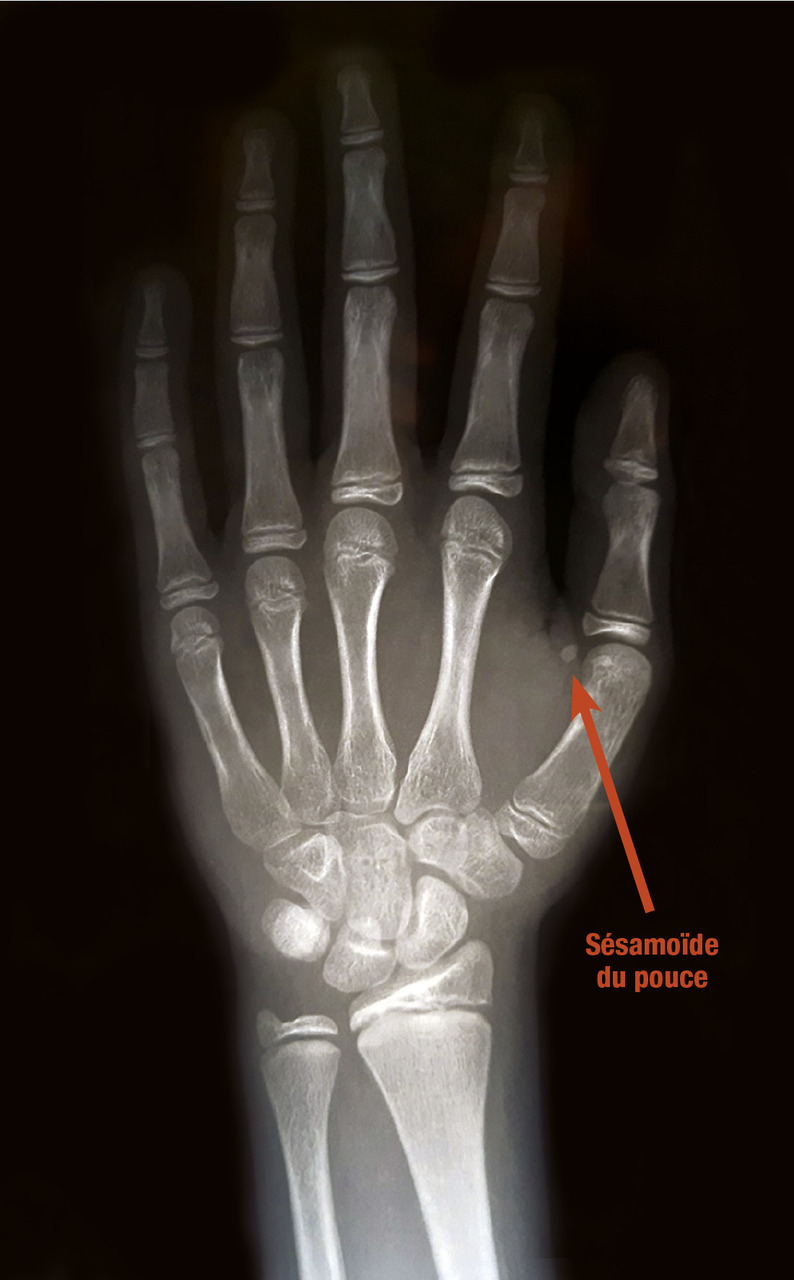

Elle permet d’obtenir un repère quantifiable de la maturation du squelette par les stéroïdes sexuels. Il est lu à l’aide d’un atlas radiologique (Greulich et Pyle), à partir d’une radiographie du poignet et de la main gauche. Le début de la puberté correspond habituellement à un âge osseux de 13 ans chez le garçon et de 11 ans chez la fille. Cet âge osseux correspond grossièrement à l’apparition du sésamoïde du pouce.

La détermination de l’âge osseux permet d’obtenir un repère quantifiable de la maturation du squelette par les stéroïdes sexuels. Il est lu à l’aide d’un atlas radiologique (Greulich et Pyle), à partir d’une radiographie du poignet et de la main gauche. Le début de la puberté correspond habituellement à un âge osseux de 13 ans chez le garçon et de 11 ans chez la fille. Cet âge osseux correspond grossièrement à l’apparition du sésamoïde du pouce. L’accélération de la maturation osseuse est la conséquence de la sécrétion des stéroïdes sexuels. Elle signe le risque de la survenue d’une puberté précoce, la soudure prématurée des cartilages de croissance entraînant un risque de petite taille définitive.